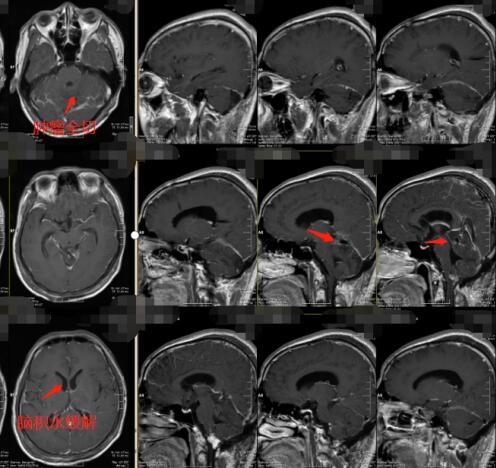

▲术后肿瘤全切、脑积水缓解